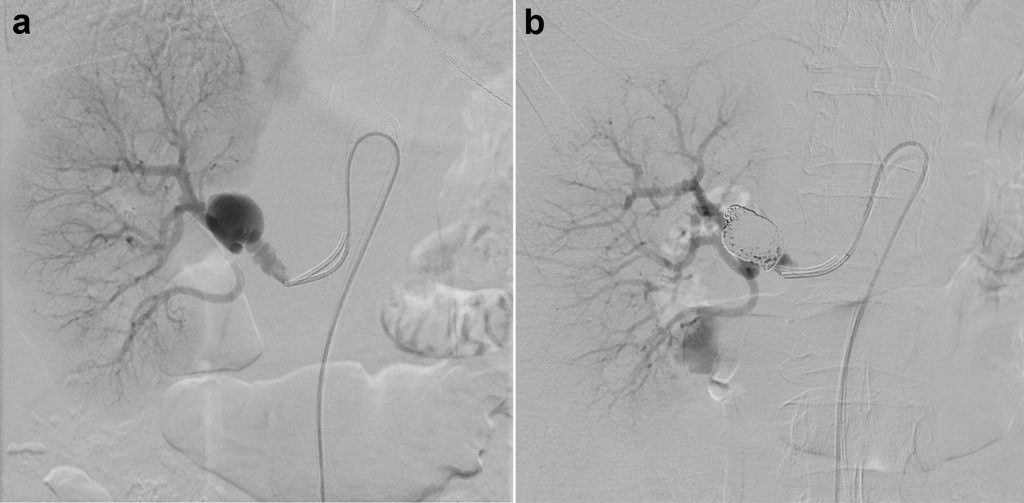

- Le tecniche chirurgiche endovascolari consistono invece in un trattamento mini-invasivo. Vengono effettuate mediante puntura di un’arteria periferica (arteria femorale o arteria omerale) e permettono, sotto controllo radiologico, di andare a posizionare stent, materiali emboligeni (es. spirali, colle) o ad effettuare dilatazioni (angioplastiche) delle arterie di interesse. Questo tipo di approccio ha mostrato buoni risultati nel breve e medio termine, con tassi di complicanze intra-operatorie minori rispetto all’approccio chirurgco tradizionale. Essendo però un trattamento di più recente utilizzo, non si conoscono con certezza le sue complicanze oltre i cinque anni dall’intervento, pur non significando ciò necessariamente una evoluzione sfavorevole.